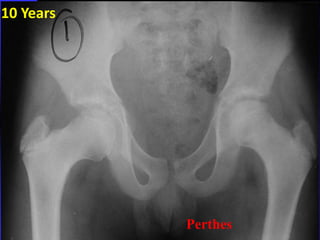

Legg-Calvé-Perthes disease

Symptoms of Perthes usually

have been present for weeks.

• Hip, groin, thigh or knee pain

• Limp :painless and intermittent.

* Slight widening of the left hip joint

* Decrease epiphyseal hight

= The F.H smaller denser on the left

= Joint widening can also be 2ry to

10 Years

Perthes